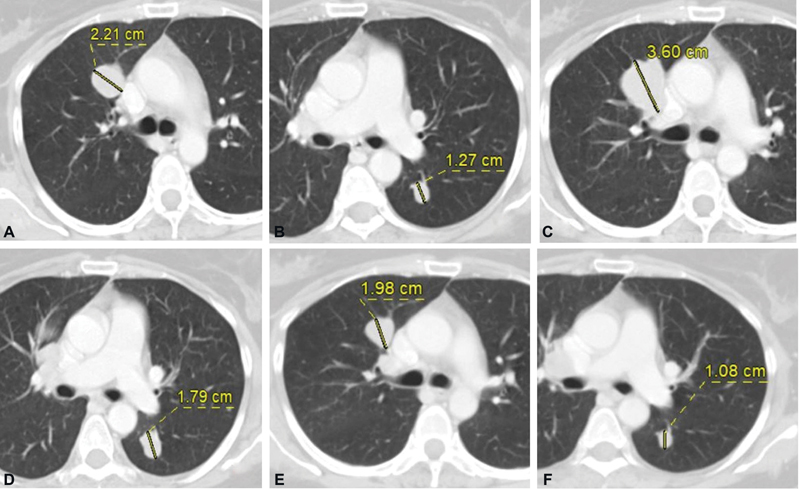

| Fig. 1(A) Metastatic right upper lobe perihilar nodule and (B) left lower lobe nodule at baseline CT. (C and D) Increase in size of these nodules after immunotherapy and decrease in size on follow-up scan (E and F).

| Fig. 1(A) Metastatic right upper lobe perihilar nodule and (B) left lower lobe nodule at baseline CT. (C and D) Increase in size of these nodules after immunotherapy and decrease in size on follow-up scan (E and F).